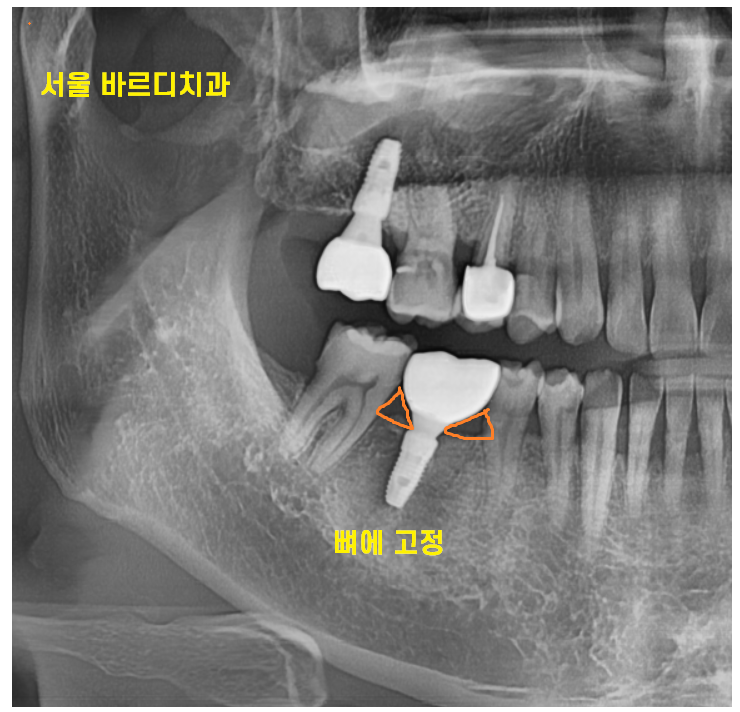

임플란트는 뼈에 박혀 고정되어 있는데

주변에 자연치아는 치주인대에 의하여

조금씩 움직이니

임플란트 음식물 끼임 발생할 수 밖에 없는거죠~~